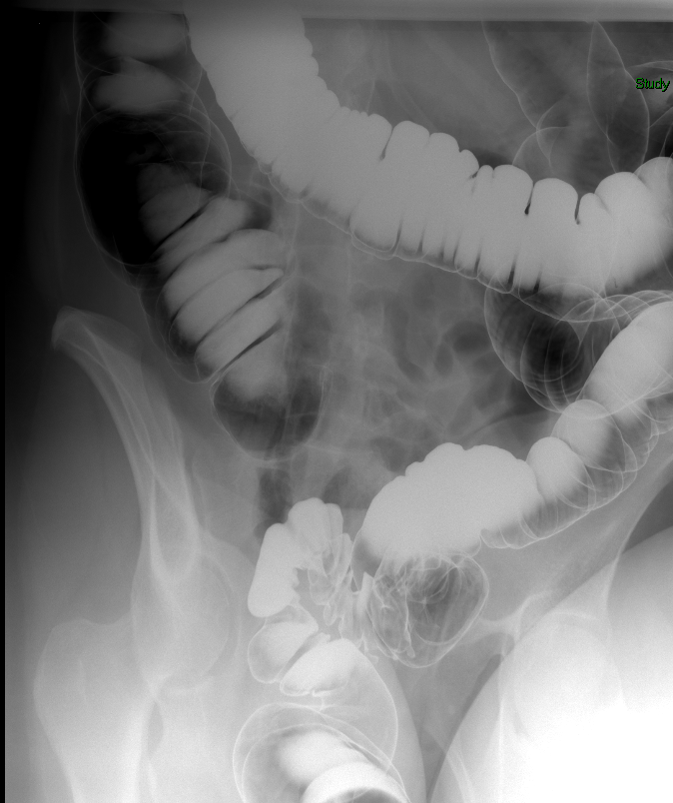

- The technologist will obtain a scout image. Assess the image for any possible contraindications such as pneumoperitoneum, evidence of ileus or obstruction, or residual contrast material

(key image 1).

- Once 15 minutes has passed since the patient drank the barium, the technologist will obtain a prone (if possible) radiograph

(key image 2).

- The technologist will obtain radiographs at 30, 45, and 60 minutes after the initial administration of barium. If the column of contrast material has not reached the large bowel on the 60 minute film, the technologist will obtain images every 30 minutes until contrast can been seen in the cecum

(key image 3)

(key image 4)

(key image 5).

- The technologist will have you review every image.

- Obtain images of the terminal ileum and the ileocecal valve filled with contrast material

(key image 6)

(key image 7)

(key image 8)

(key image 9)

(key image 10).

- Obtain spot images of the remainder of the small bowel

(key image 11)

(key image 12)

(key image 13)

(key image 14).

- Obtain images of all four quadrants. Use the compression paddle to separate loops of small bowel from each other.